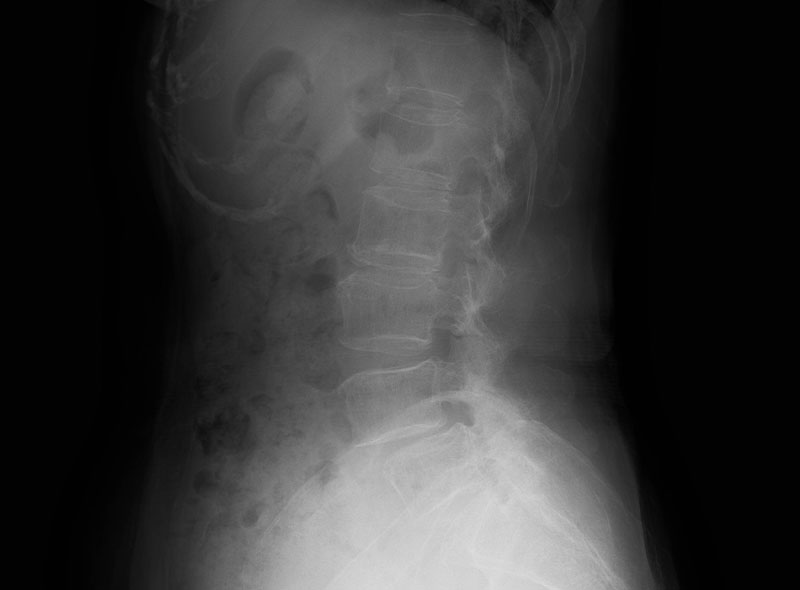

デジタルX線画像診断装置

画像の拡大縮小や濃度調整ができるため診断精度が向上し、わかりやすい説明も可能です。

腰(腰椎すべり症)